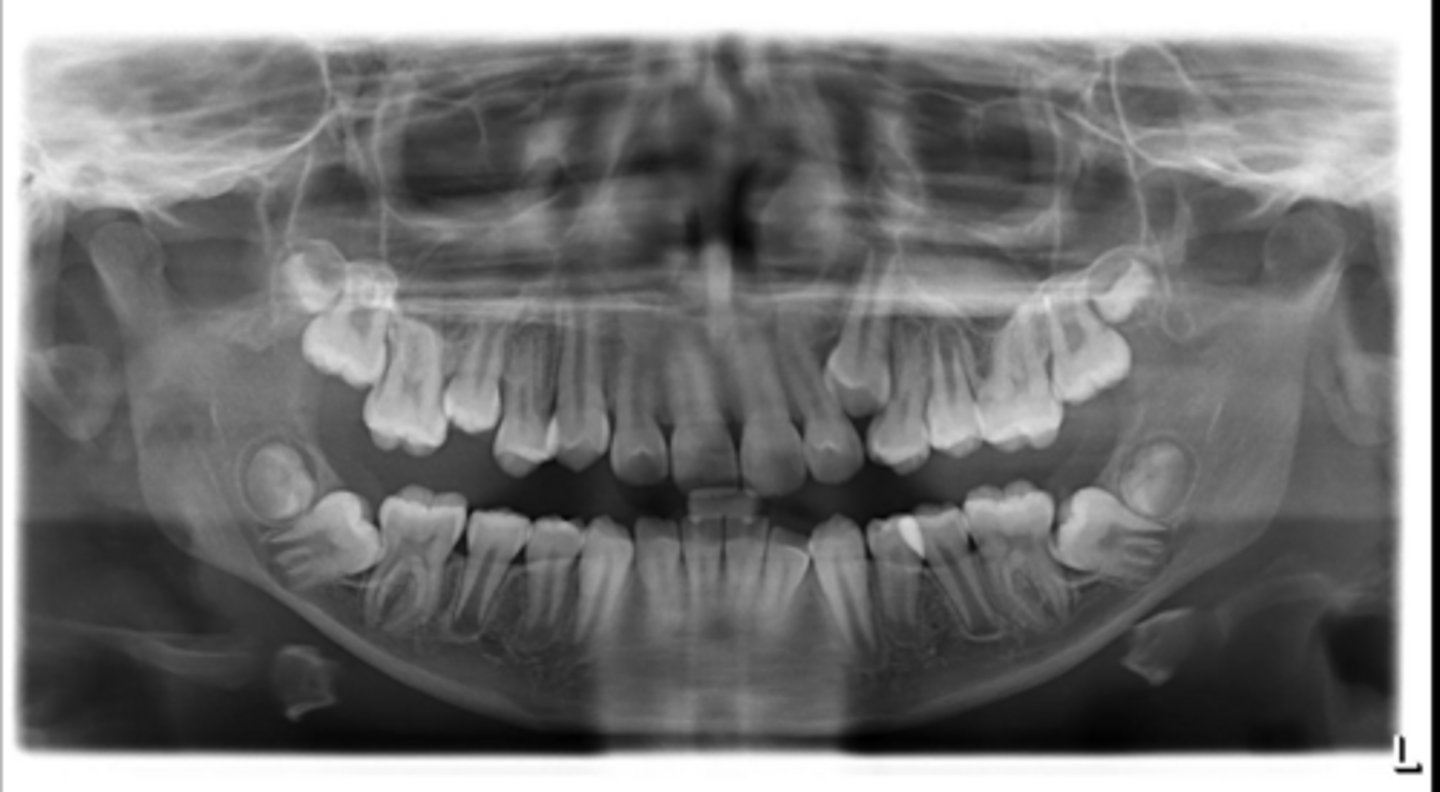

No

Are there congenitally missing teeth in the maxillary arch?

Are there congentially missing teeth in the mandibular arch?

Any supernumerary teeth?

Yes - mandibular second molars

Any impacted teeth?

Yes

Are the condyles symmetrical?

Maybe in the upper molars

Are there any dilacerated roots?

Are there congenitally missing teeth in the mandibular arch?

Are there any supernumerary teeth?

Are there retained primary teeth?

A little bit

Is there crowding?

Is there any pathology?

Possibly #20